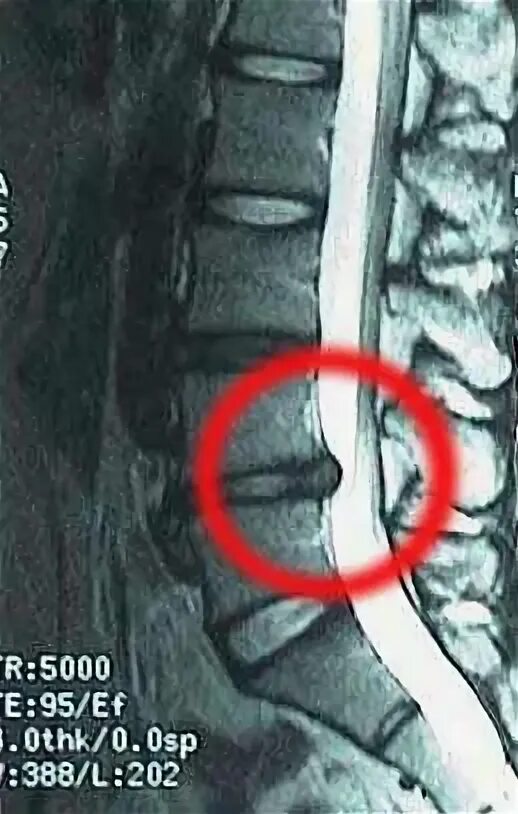

Дегенерация межпозвонкового диска по pfirrmann